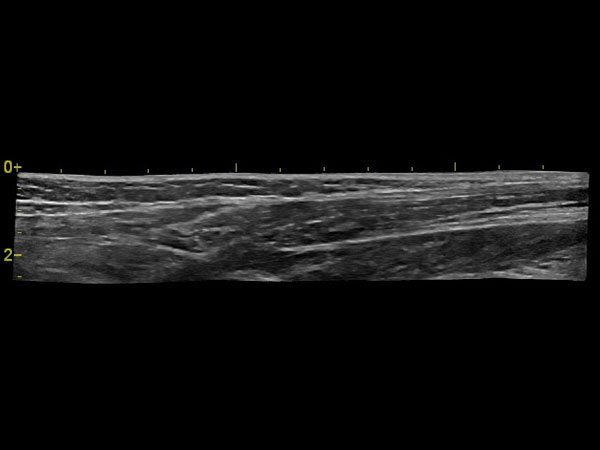

• ангиология;

• скелетно-мышечная система;

• Линейный датчик GE L6-12-RS

• Линейный датчик GE 9L-RS

• Линейный датчик GE 12L-RS

• Интраоперационный линейный датчик GE L8-18i-RS